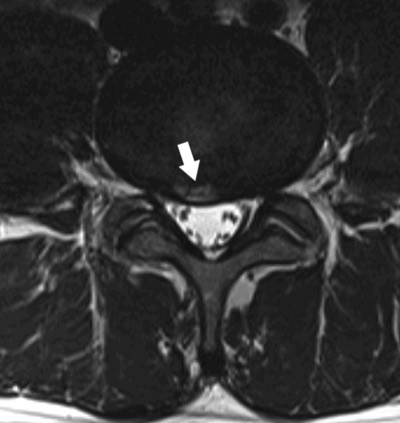

Annulusrupturer er konsentriske eller radiære sprekker i anulus fibrosus. De ses på T2-vektede MR-bilder som områder med høyt signal i kanten av skiven (high intensity zone, HIZ), typisk i midtlinjen inn mot spinalkanalen i de nederste lumbale skivene (fig 2). Det har vært hevdet at annulusruptur kan gi ryggsmerter gjennom enten direkte mekanisk påvirkning av smerteførende fibre i kanten av skiven eller ved lekkasje av inflammatorisk aktive substanser fra nucleus pulposus (13). Imidlertid er dette et hyppig funn også hos asymptomatiske personer. I en normalpopulasjon av 40-åringer i Danmark (15) hadde ca. 40 % annulusruptur, og det var bare en moderat assosiasjon med kroniske ryggsmerter. Funn av slike rupturer på MR-bilder må ses som en del av utviklingen av skivedegenerasjon, men funnet i seg selv kan ikke tillegges noen vesentlig betydning som årsak til symptomer.